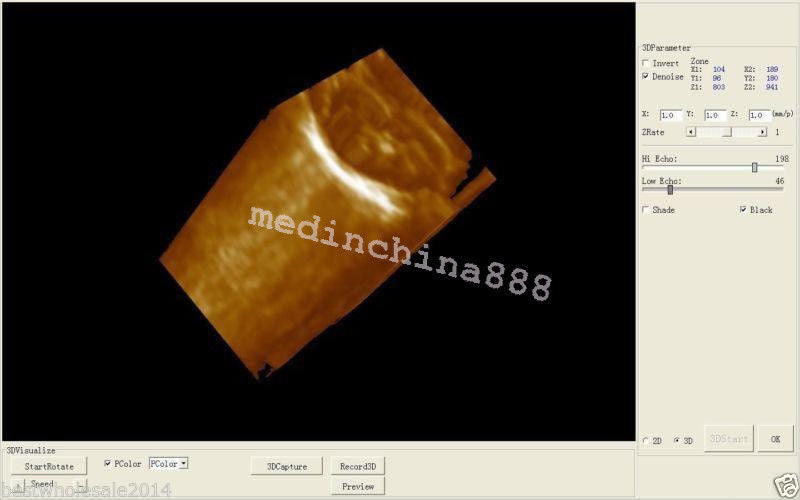

Image mode: B, B+B, 4B, B+M, M